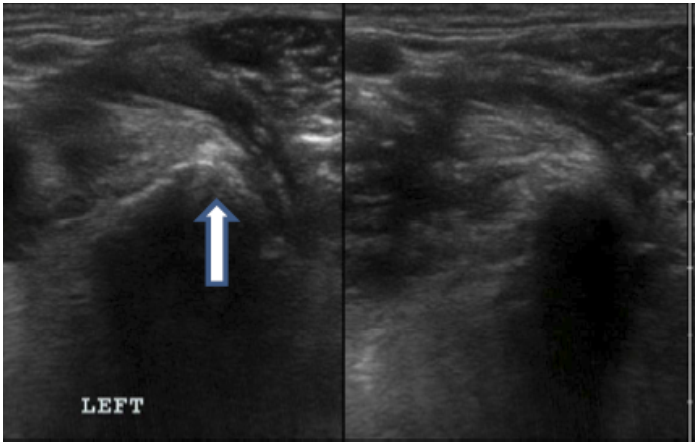

Objective: Iliopsoas injury and strain is a commonly diagnosed disease process, especially amongst working and sporting canines. There has been very little published literature regarding iliopsoas injuries and there is no information regarding the ultrasound evaluation of abnormal iliopsoas muscles. This manuscript is intended to describe the ultrasound findings in 73 canine agility athletes who had physical examination findings consistent with iliopsoas discomfort. The population was chosen given the high incidence of these animals for the development of iliopsoas injury; likely due to repetitive stress.

Methods: Medical records of 73 agility performance canines that underwent musculoskeletal ultrasound evaluation of bilateral iliopsoas muscle groups were retrospectively reviewed. Data included signalment, previous radiographic findings, and ultrasound findings. A 3-tier grading scheme for acute strains was used while the practitioner also evaluated for evidence of chronic injury and bursitis.

Results: The majority of pathologies were localised to the tendon of insertion, with the majority being low grade I-II strains (80.8%). Tendon fibre disruption (71.2%) and indistinct hypoechoic lesions (91.8%) were the most common of acute changes noted. Hyperechoic chronic changes were noted in 84.9 percent of cases. Acute and chronic changes were commonly seen together (62.8%).

Conclusion: Diagnostic musculoskeletal ultrasound was used to identify lesions of the iliopsoas tendon consistent with acute and chronic injury, as well as identifying the region of pathology. The majority of agility performance dogs had low grade acute strains based on the tiered system, with mixed acute and chronic lesions being noted frequently.

Application: Diagnostic musculoskeletal ultrasound provides a non-invasive diagnostic modality for patients suspected of having an iliopsoas strain.